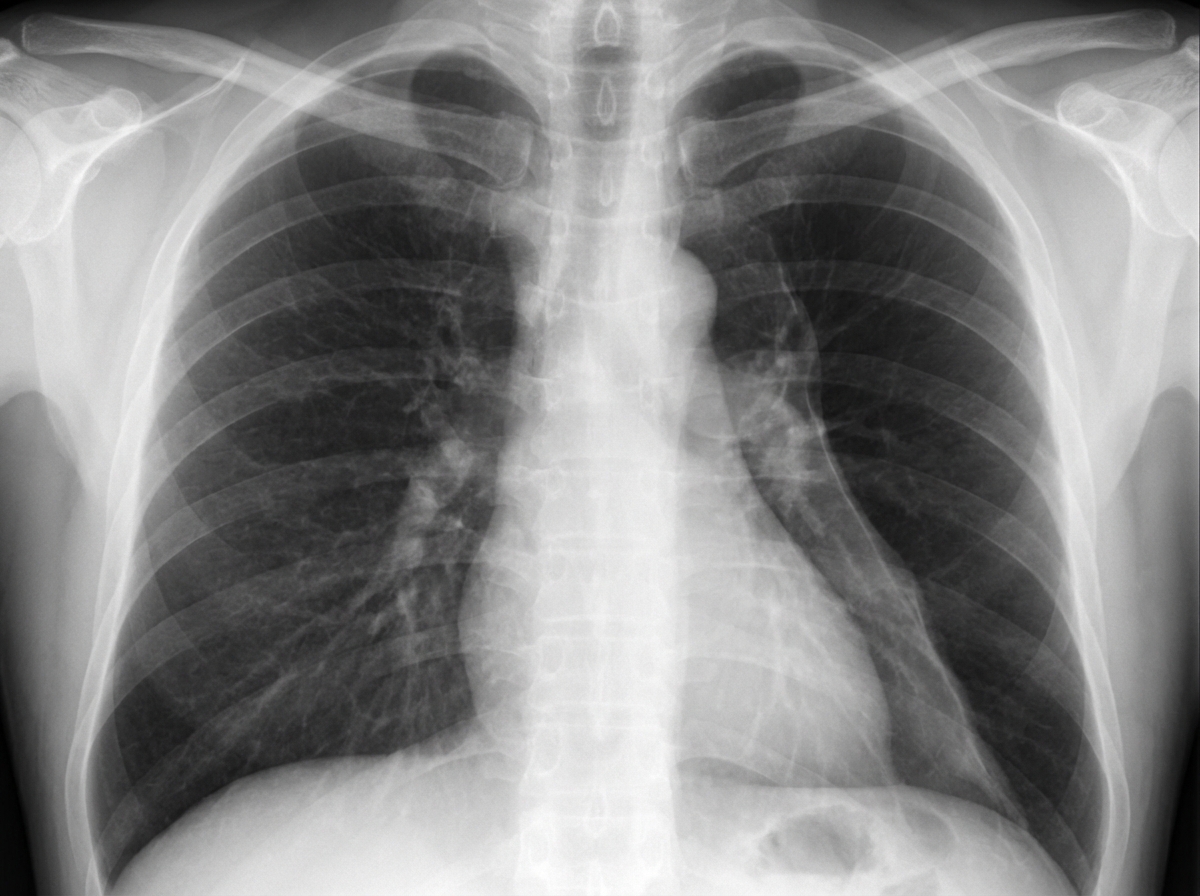

A 19-year-old man comes to the emergency department with sharp, left-sided chest pain and shortness of breath. He has no history of recent trauma. He does not smoke or use illicit drugs. He is 196 cm (6 feet 5 in) tall and weighs 70 kg (154 lb); BMI is 18 kg/m2. Examination shows reduced breath sounds over the left lung field. An x-ray of the chest is shown. Which of the following changes is most likely to immediately result from this patient's current condition?